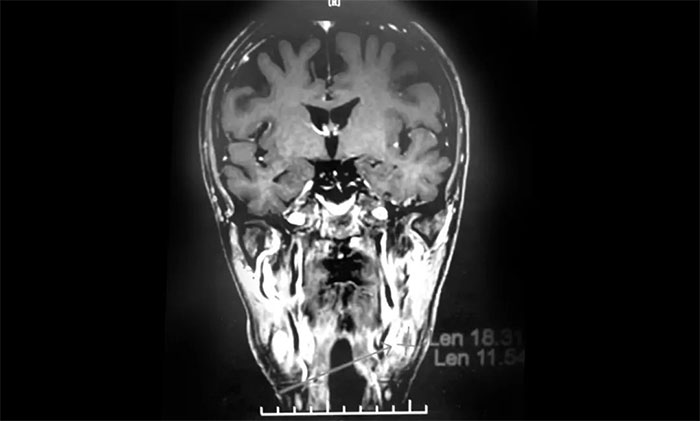

经MDT多学科会诊评估,制定以放疗为主的同步放化疗方案。治疗后复查MRI,患者左侧鼻咽部实性占位较前治疗明显减小;原左侧下颌腺区、咽旁肿大淋巴结已基本吸收好转,左颈部肿大淋巴结较前明显缩小。

▲ 放疗后复查MRI,肿瘤占位较前明显减小